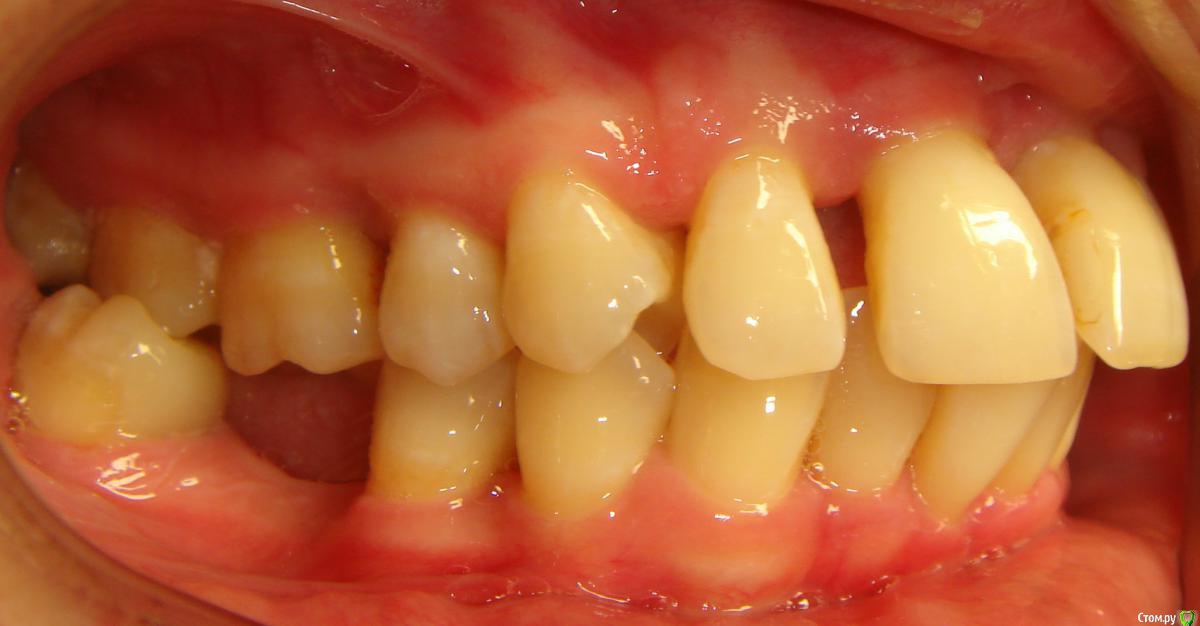

Opdihatop Опубликовано 9 мая, 2016 Поделиться Опубликовано 9 мая, 2016 (изменено) Здравствуйте, коллеги! Хотел бы представить вашему вниманию вот такой вот случай и спросить совета. В принципе, по окклюзии ничего особенного по лечению нет, но вот проблемы с пародонтом (на КТ по кости все заметно хуже, чем на орто), делают невозможным все, продуманные мной варианты. Может у кого-то было что-то подобное? Может поделитесь советом, а то помочь человеку надо, а я в тупике. Буду заранее очень благодарен за помощь! Изменено 9 мая, 2016 пользователем Opdihatop Ссылка на комментарий

Opdihatop Опубликовано 13 мая, 2016 Автор Поделиться Опубликовано 13 мая, 2016 чтобы вывести в первый класс, для этого надо челюсть поставить в первый класс. (проблема не в положении зубов, а положении челюсти), что вам мешает это сделать? Да нет, тут как раз проблема в зубах, так как из-за вторичной адентии 13 зуба фронт верха уехал вправо, да и правый боковой сегмент немного мезиализировался. Как тут поможет постановка челюсти в первый класс? Даже если бы вышеупомянутой проблемы по зубам не было бы, то для постановки челюсти эластиков скорее всего не хватило бы, а корректоры второго класса с таким пародонтом я ставить не рискнул бы.Вот в связи с этим и возник вопрос по первому классу, так как дистализировать не получится и удалять нельзя, потому что с таким пародонтом промежутки не закроются... Ссылка на комментарий

Yana guapa Опубликовано 13 мая, 2016 Поделиться Опубликовано 13 мая, 2016 Да нет, тут как раз проблема в зубах, так как из-за вторичной адентии 13 зуба фронт верха уехал вправо, да и правый боковой сегмент немного мезиализировался. Как тут поможет постановка челюсти в первый класс? Даже если бы вышеупомянутой проблемы по зубам не было бы, то для постановки челюсти эластиков скорее всего не хватило бы, а корректоры второго класса с таким пародонтом я ставить не рискнул бы.Вот в связи с этим и возник вопрос по первому классу, так как дистализировать не получится и удалять нельзя, потому что с таким пародонтом промежутки не закроются... Здесь чистый второй класс. Расчет ТРГ и индекс APDI Вам ясно это дают понять. конечно об эластиках речь не идет (я из вообще не применяю, только корректоры). Но не всегда первый класс - панацея. Зависит от того, какую вообще цель преследуете. Иногда можно оставить в привычном втором классе и со спокойной совестью отпустить)))))) Ссылка на комментарий